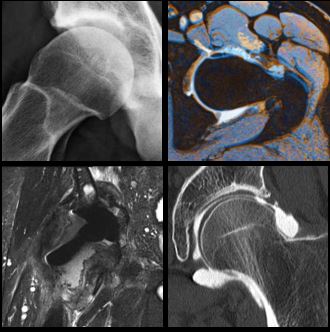

"2nd SSSR Educational Meeting - 2ème Symposium d'Imagerie Musculoscquelettique"

Samedi 27 juin 2015 - 8h30-14h

Auditoire César Roux, CHUV, Lausanne

Dr Fabio BECCE & Dr Patrick OMOUMI

- Programme (pdf)

- Syllabus du cours (pdf)

"Symposium d'imagerie musculosquelettique"

Samedi 24 mai 2014 - 8h30-13h30

Auditoire Charlotte OLIVIER, CHUV BH-08, Lausanne

Dr Fabio BECCE & Dr Patrick OMOUMI

- Programme (pdf)

- Syllabus du cours (pdf)